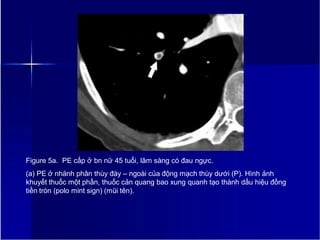

Figure 5a. PE cấp ở bn nữ 45 tuổi, lâm sàng có đau ngực.

(a) PE ở nhánh phân thùy đáy – ngoài của động mạch thùy dưới (P). Hình ảnh

khuyết thuốc một phần, thuốc cản quang bao xung quanh tạo thành dấu hiệu đồng

tiền tròn (polo mint sign) (mũi tên).